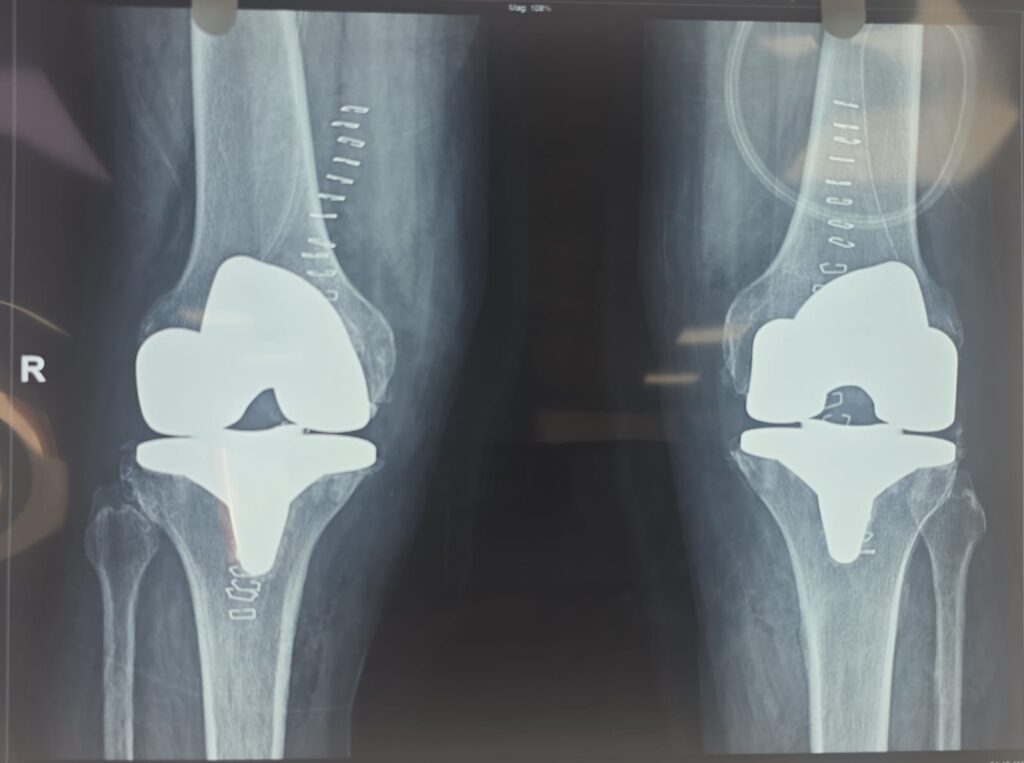

Robotic Joint Replacement Surgery

- Robotic Total Knee Replacement (TKR)

- Partial Knee Replacement (Robotic Assisted)

- Revision Joint Replacement with Robotics

Conventional Joint Replacement Surgery

- Total Knee Replacement (Conventional)